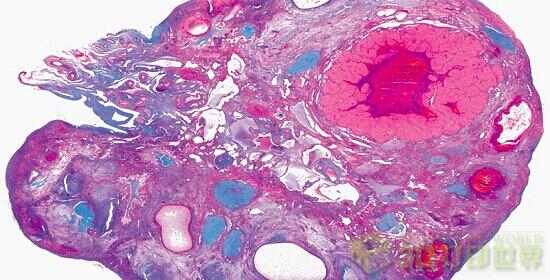

最后给广大不孕不育的女性朋友报告一个不是黑科技的好消息,

美国西北大学的科学家们使用一台3D打印机制造了一个人造卵巢,

并将其植入一个原有卵巢已经被切除的小鼠,该小鼠后来成功受孕了,并产下幼崽哟。

图是什么鬼!!!

研究人员希望利用这个技术开发一个卵巢生物假体,并将其植入女性体内以恢复其生育能力。